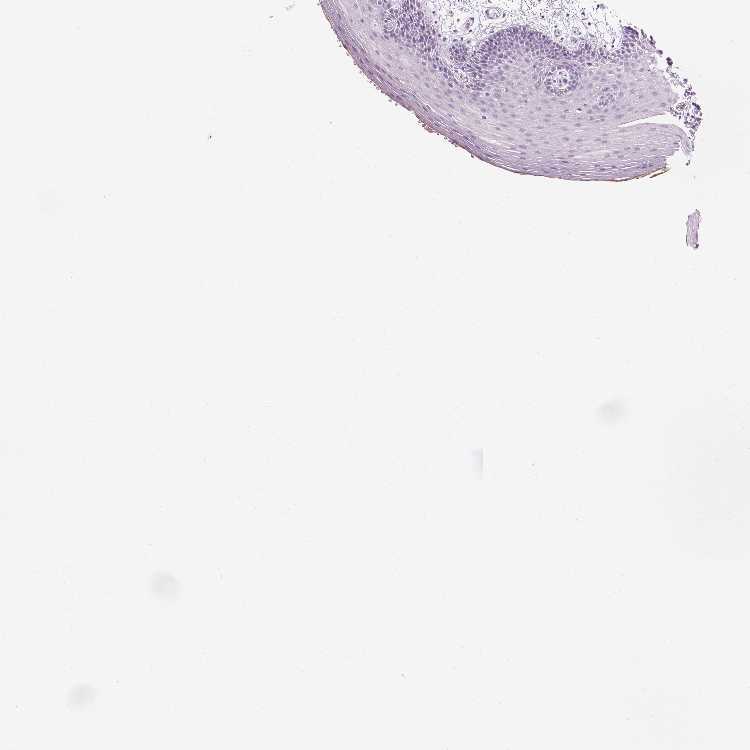

TISSUE PRIMARY DATA ORAL MUCOSA Show tissue menu

ORAL MUCOSA - Antibody stainingi

Antibody staining in the annotated cell types in the current human tissue is reported as not detected, low, medium, or high, based on conventional immunohistochemistry profiling in selected tissues. This score is based on the combination of the staining intensity and fraction of stained cells.

Each image is clickable and will lead to virtual microscopy that enables deeper exploration of all samples and also displays staining intensity scores, fraction scores and subcellular localization as well as patient and tissue information for each sample.

Antibody HPA039486Antibody HPA048186

Squamous epithelial cells Not detectedNot detected